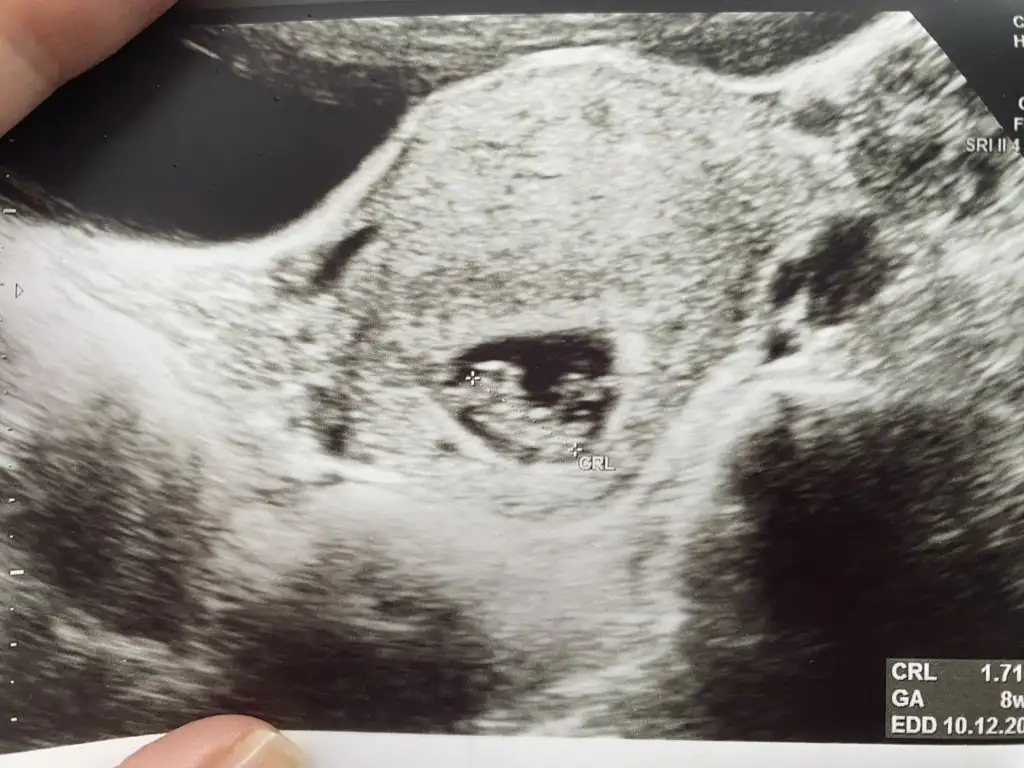

Ben hala nub teorisi cözemenlerdenim 😅 banada cinsiyet tahmini yapabilirmisiniz lutfen

Merhabalar, 8+3 haftalık ve karından ultrason. Sizce cinsiyeti ne olabilir acaba?😬